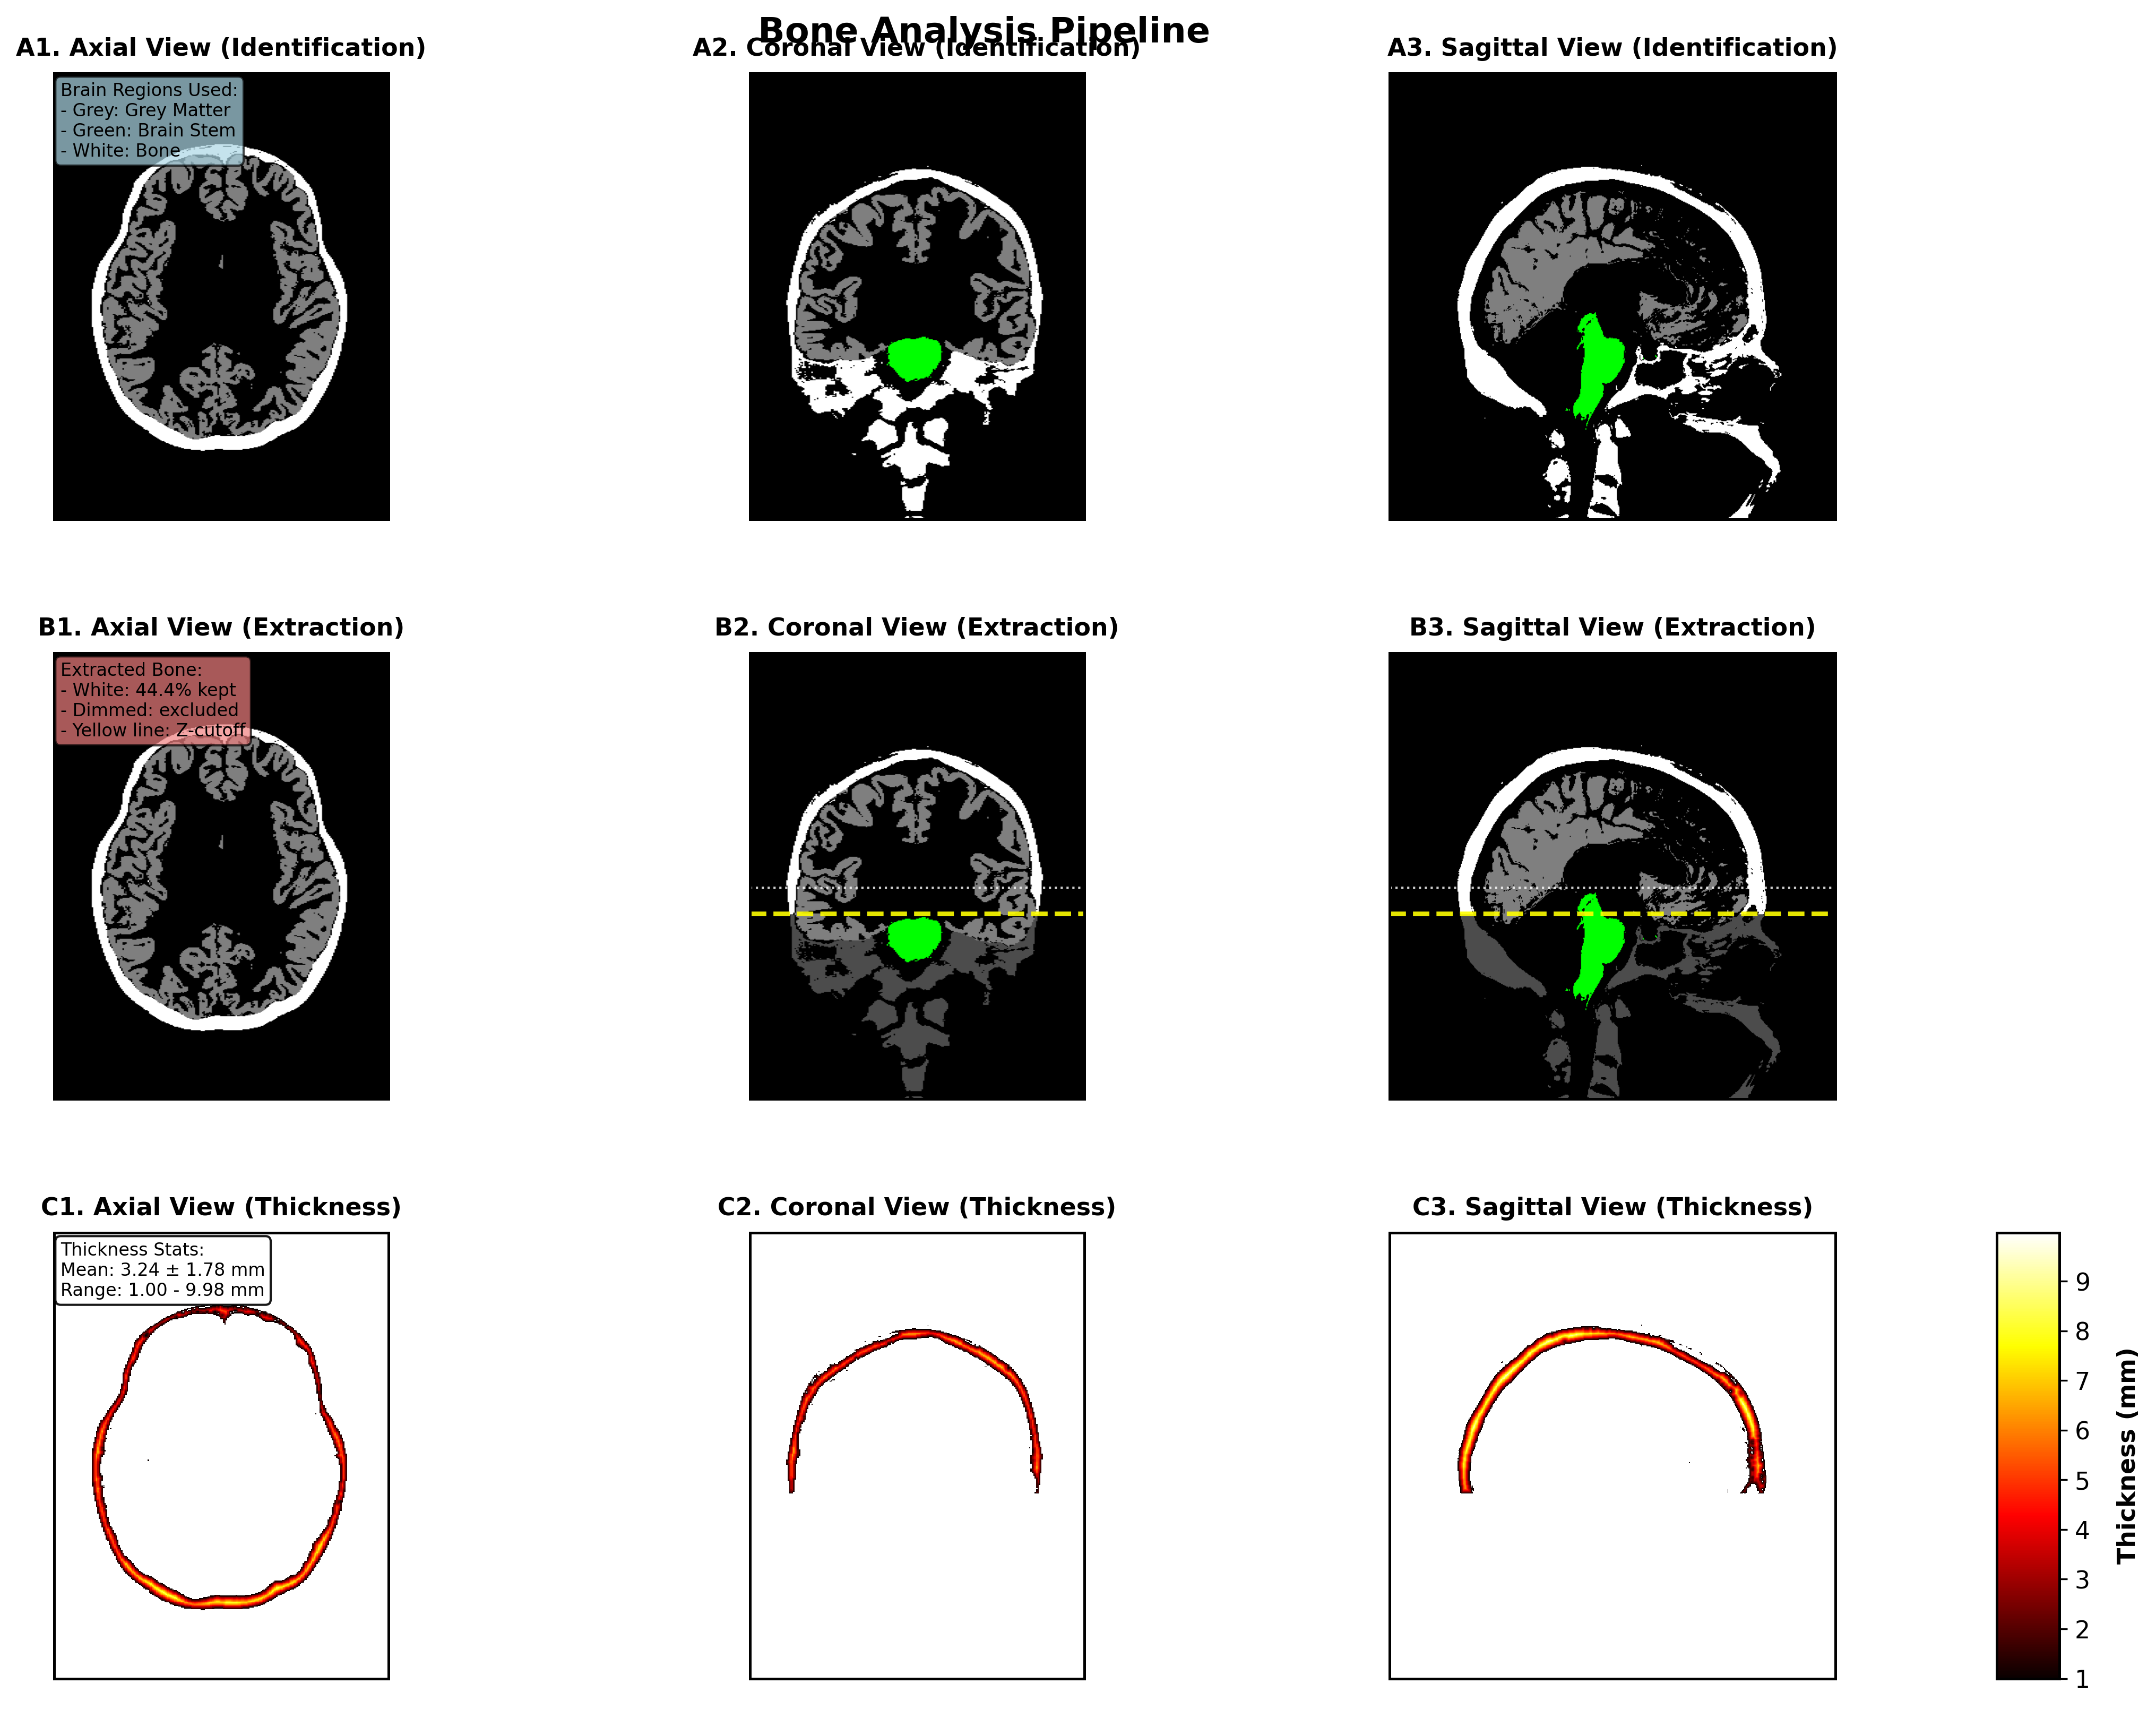

Analysis Pipeline

1. Tissue Identification

- Load segmented NIfTI data from SimNIBS derivatives

- Extract tissue masks using configured label numbers

- Load label names from labeling_LUT.txt for human-readable output

2. Spatial Filtering

- Identify brain reference regions (cortex and brainstem)

- Apply 3D bounding box with configurable padding

- Filter out lower anatomy using Z-coordinate thresholds

- Focus analysis on relevant anatomical regions

3. Analysis

- Calculate total tissue volume / thickness (experimental)

- 3D Thickness Analysis: Distance transform-based thickness calculations with statistical summaries (experimental)

- Publication-Quality Visualizations: High-resolution figures for axial, coronal, and sagittal views